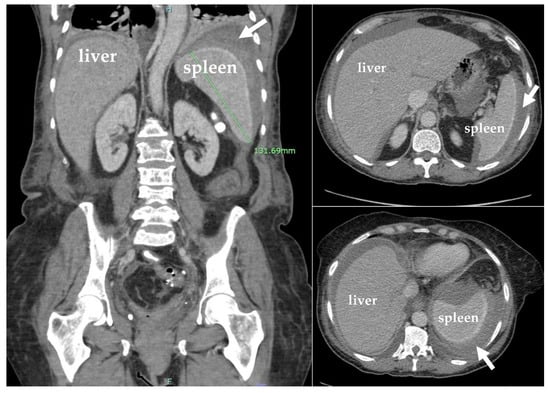

Computed tomography (CT) of the abdomen and pelvis revealed hepatomegaly of 23 cm with no other acute findings (Figure 2). During hospitalization, hemoglobin dropped to 6.1 g/dL, requiring transfusion of a unit of packed RBC, which improved hemoglobin to 7.0 g/dL. The nausea and vomiting persisted, warranting a repeat CT of the abdomen and pelvis, which showed new development of hemoperitoneum in the left abdomen surrounding the spleen, leading to concerns about subcapsular hematoma and an enlarged spleen by 13.2 cm (Figure 3). Additionally, the patient developed dyspnea, and chest X-ray revealed a pleural effusion in the left lung base.

Figure 2. Coronal plane computed tomography (CT) scan with IV contrast of the abdomen and pelvis showing hepatomegaly (23 cm). Spleen was normal.

Figure 3. Coronal and sagittal plane computed tomography (CT) scans with IV contrast of the abdomen and pelvis showing hemoperitoneum (white arrows) and mild splenomegaly (13.2 cm).